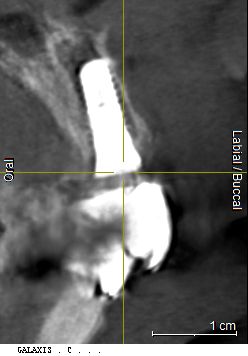

Verwendet wurde im vorliegenden Fall das Implantatsystem Procone (Medentika). Die Aufbereitung des Implantatbettes regio 11 erfolgte nach Bohrprotokoll bis zum Durchmesser 4,3 mm. Der Spalt zum fazialen Knochen wurde mit einem bovinen Augmentat (Cerabone, Straumann) gefüllt. Zur verbesserten Wundheilung sind sowohl das Implantat als auch das Cerabone vor dem Einsetzen mit patienteneigenem Blutplasma bzw. Wachstumsfaktoren (iPRF) benetzt worden (Abb. 7 und 8). Das Implantat wurde nach dem Gewindeschneiden palatinal orientiert inseriert, sodass der Einbringpfosten bukkal hinter der fazialen Fläche der Nachbarzähne platziert war. Der Verschluss erfolgte erstmal mit einer Einheilkappe (Höhe 2 mm) (Abb. 9).

Eine radiologische Kontrolle bestätigte die Ossifikation des Implantats. Nach der Eröffnung der Situation konnte die unter der Gingiva liegende Einheilkappe (2 mm) regio 11 gegen eine höhere Einheilkappe (4 mm) ausgetauscht werden. Ziel war es, das Weichgewebe zu konditionieren und eine gute Basis für ein natürliches Emergenzprofil zu schaffen. Zehn Tage später wurde die Situation mit Abformpfosten und offenem individuellem Löffel abgeformt (Impregum, 3M). Das Implantat wurde mit einem provisorischen Abformpfosten aus PEEK versorgt und eine Chairside gefertigte provisorische Krone eingegliedert. Die Herstellung der definitiven implantatprothetischen Versorgung erfolgte im Dentallabor. Nach einer Woche konnte die provisorische Restauration entfernt und die keramische Implantatkrone mit Carboxylatzement (Durelon, 3M) zementiert werden (Abb. 15 und 16). Hierbei wurde auf die gründliche Entfernung der Zementreste geachtet und die saubere Fuge im Röntgenbild nochmals geprüft. Mit der implantatprothetischen Restauration ist der Patient in ästhetischer sowie funktioneller Hinsicht sehr zufrieden (Abb. 17 und 18).